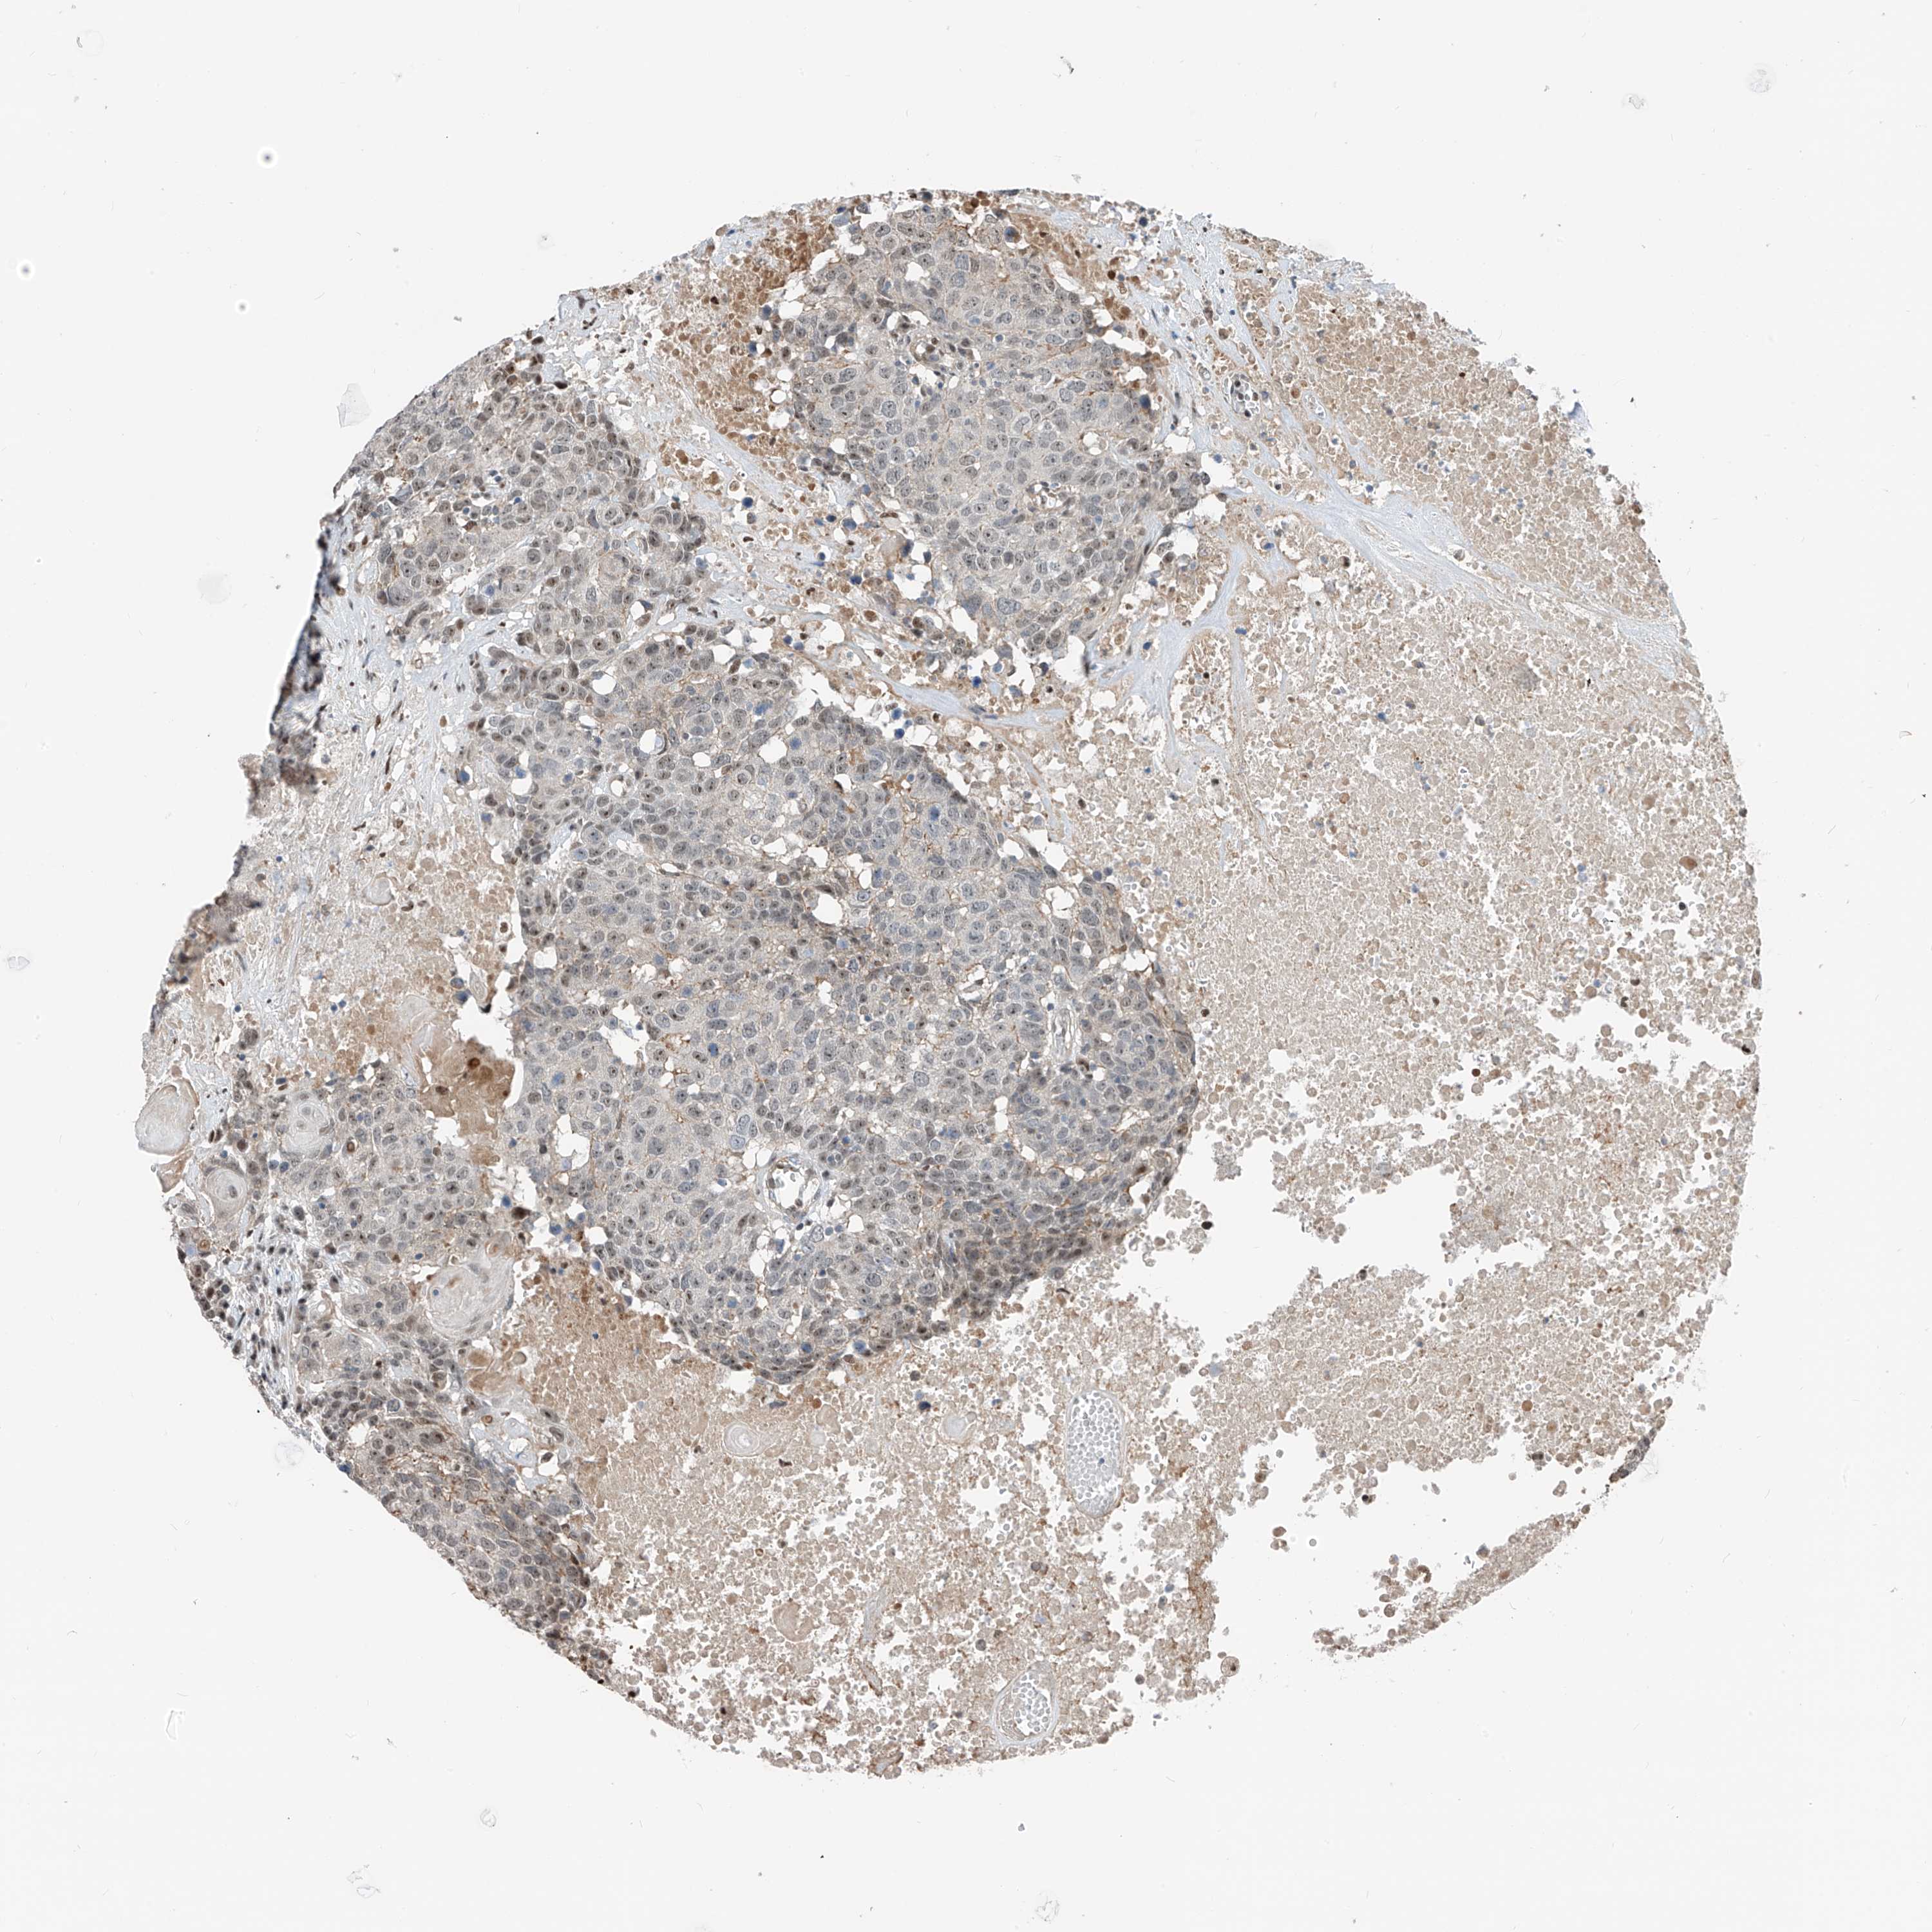

HEAD AND NECK CANCER - Protein expressioni

A mouse-over function shows sample information and annotation data. Click on an image to view it in a full screen mode. Samples can be filtered based on level of antibody staining by selecting one or several of the following categories: high, medium, low and not detected. The assay and annotation is described here.

Antibody stainingi

Antibody staining in the annotated cell types in the current human tissue is reported as not detected, low, medium, or high, based on conventional immunohistochemistry profiling in selected tissues. This score is based on the combination of the staining intensity and fraction of stained cells.

Each image is clickable and will lead to virtual microscopy that enables deeper exploration of all samples and also displays staining intensity scores, fraction scores and subcellular localization as well as patient and tissue information for each sample.

Antibody HPA034749

Staining

High

Medium

Low

Not detected

Intensity

Strong

Moderate

Weak

Negative

Quantity

>75%

75%-25%

<25%

None

Location

Nuclear

Cytoplasmic/membranous

Cytoplasmic/membranous,nuclear

Squamous cell carcinoma, NOS

Squamous cell carcinoma, metastatic, NOS

Adenocarcinoma, NOS